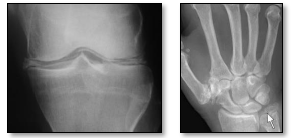

Paciente feminina, 68 anos, vai à consulta devido à queixa de dor e edema em punho esquerdo, de início há 2 dias. Relata episódio prévio semelhante há 8 meses em joelho direito, que durou 2 semanas, sem melhora com uso de anti-inflamatórios e com resolução espontânea. Refere como comorbidades diabetes insulinodependente e hipotireoidismo. A paciente apresenta ao médico duas radiografias realizadas em UBS, as quais são evidenciadas a seguir. Qual é o provável diagnóstico?